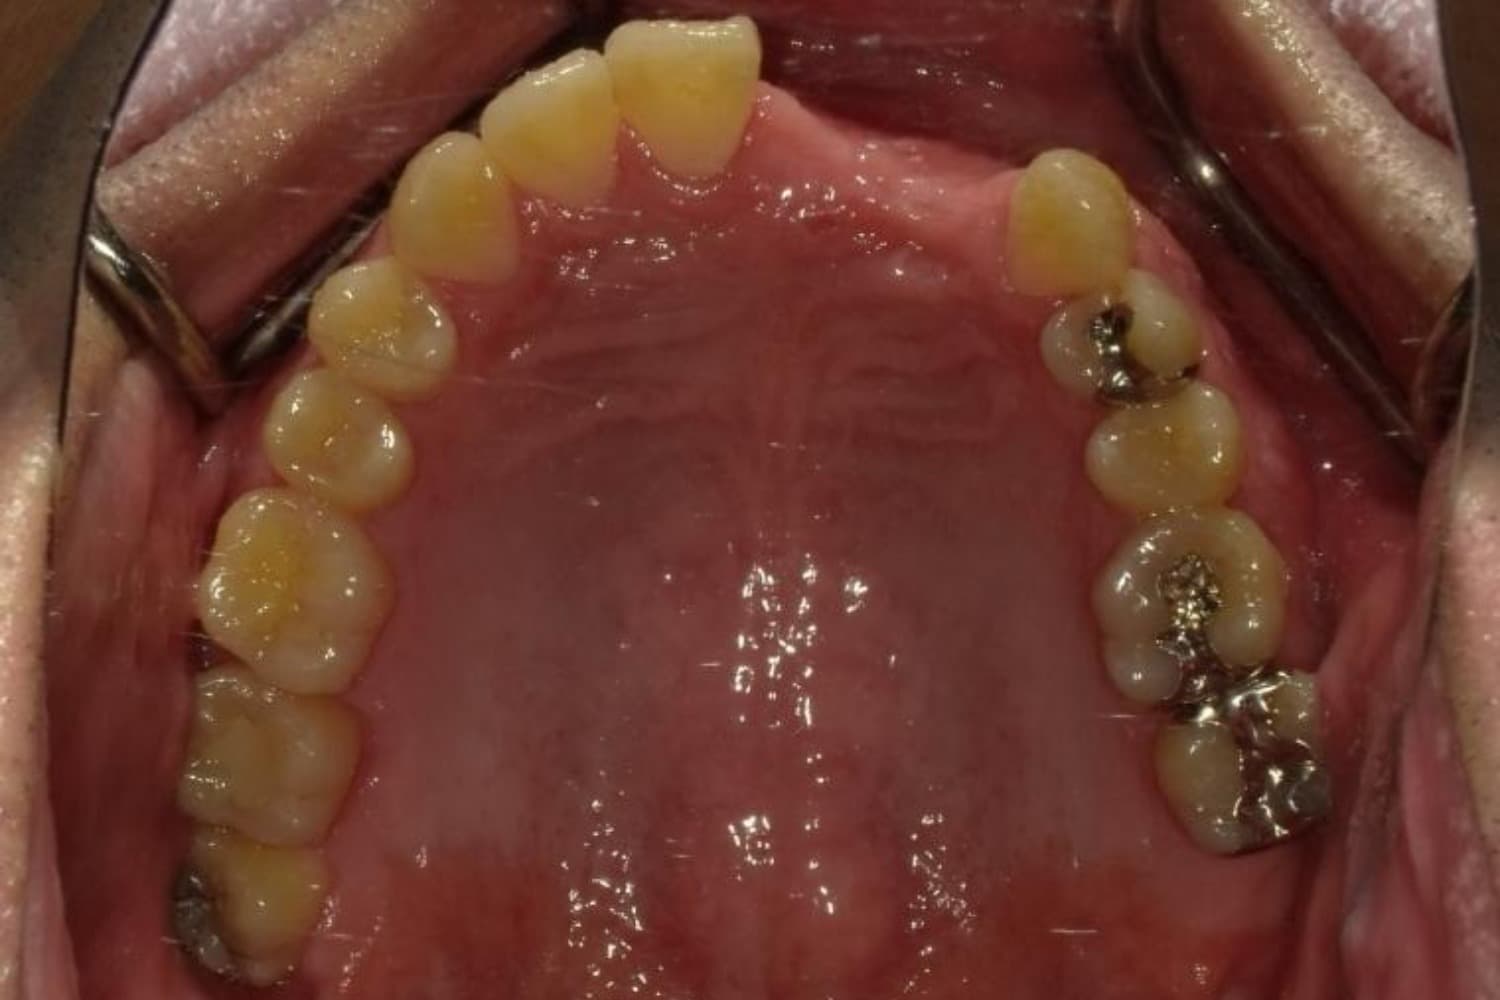

下顎大臼歯3本欠損症例

Before

左下第一大臼歯は保存が困難な状態であったため抜歯をおこないました。あわせて、ご来院時から欠損していた右下第一・第二大臼歯も含め、欠損部の補綴方法についてご説明し、インプラント治療を選択されました。

年齢

60歳

性別

男性

主訴

左下の第一大臼歯は別の医院で治療中でしたが、治療が思うように進まず、加えて他の箇所にも痛みが続いたことから、当院にご相談いただきました。

治療期間

10ヵ月

費用

140万円

副作用・リスク

インプラント治療は外科的な処置を伴い、多少の腫れや痛みが出ることがあります。 多くの場合は鎮痛薬で和らげることができます。